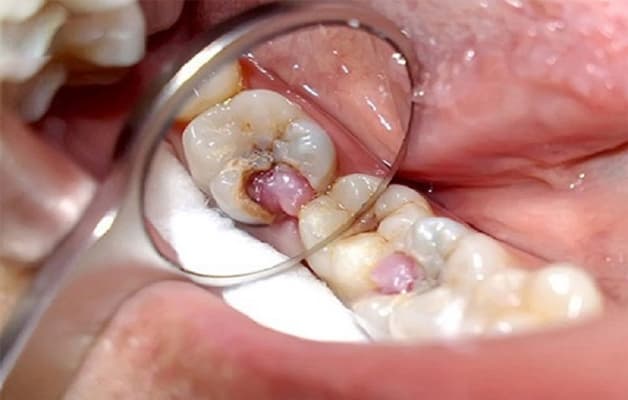

Hiện tượng thịt mọc trong răng sâu (răng sâu lồi thịt) là biến chứng do sâu răng lâu ngày không được điều trị

Hiện tượng thịt mọc trong răng sâu hay còn gọi là răng sâu lồi thịt. Đây là tình trạng khi phần nướu răng xuất hiện cục thịt thừa do bệnh sâu răng lâu ngày không được điều trị gây nên. Cục thịt mọc lên này chính là vùng niêm mạc đã bị chảy mủ và sưng to. Răng sâu lồi thịt có thể coi là một kiểu áp xe răng. Mức độ ảnh hưởng của bệnh có thể tới tủy và thậm chí gây chết tủy.

Sâu răng lồi thịt là một trong những triệu chứng phổ biến của sâu răng mức độ nặng. Cụ thể đó là giai đoạn nguy cấp khiến viêm tủy răng nặng. Ở giai đoạn này, răng sâu đến tủy và gây tình trạng đau nhức. Thậm chí cơn đau có thể lan ra toàn hàm kèm sốt nhẹ, đau đầu. Vị trí răng bị sâu đã chuyển màu đen và bị vỡ mất một phần. Khi này, vi khuẩn sẽ tấn công rất mạnh mẽ dẫn tới viêm tủy răng và hoại tử tủy. Một khi phần tủy răng đã chết, vị trí răng bị sâu sẽ không còn thấy đau nhức. Thay vào đó, một cục mủ như thịt lồi sẽ được hình thành.